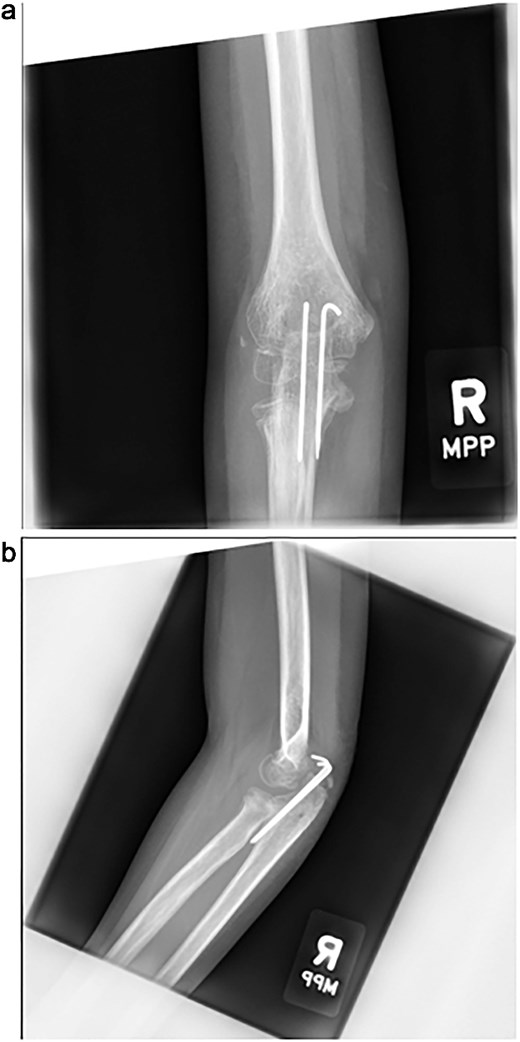

Initial radiographs following closed reduction and casting demonstrated fractures of the proximal ulna and radial neck, with improved alignment but limited bony detail (Fig. 1a and b). Elbow effusion was also noted. A CT scan performed 3 days later showed 18° apex-medial angulation of the radial neck fracture, slight inferior subluxation of the radial head, and linear calcification near the ulnotrochlear interval, concerning for an intra-articular fragment (Fig. 2).

(a, b) Initial radiographs after closed reduction, showing proximal ulna and radial neck fractures.